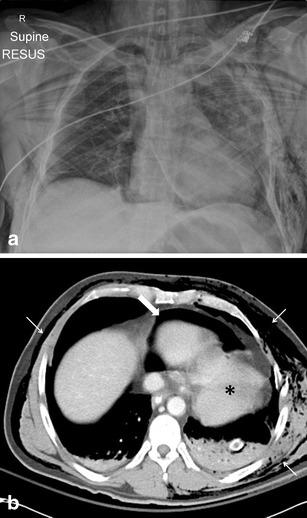

Thoracic injuries are the third most common injuries in trauma patients with cardiac injuries amongst the most lethal. Imaging is essential in diagnosis and triage of patients with pericardial injuries, and this review aims to highlight the spectrum of imaging findings of pericardial trauma. Focussed assessment with sonography for trauma (FAST) is the preferred initial examination, being rapid and accurate. Sensitivity of FAST for pericardial fluid detection is high with reported sensitivities of 97-100%. Plain chest radiography has low sensitivity for pericardial injuries but is useful in the evaluation of associated injuries. Computed tomography (CT) is the modality of choice for stable patients and can accurately diagnose traumatic pathology of the pericardium being especially useful in identification of cardiac herniation. The spectrum of CT findings includes pericardial fluid collections, focal pericardial defects and pneumopericardium.

A selection of cases of pericardial trauma encountered at a level one trauma centre is presented. Operative findings were correlated with the FAST scan, plain radiography and computed tomography imaging.

The imaging findings of pericardial trauma with various imaging modalities (ultrasound, plain radiography and computed tomography) are presented in order to aid interpretation during the acute trauma setting.